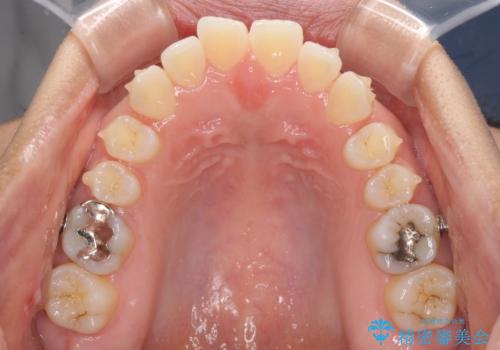

受け口傾向の前歯 すきっ歯の改善

- 前歯の隙間と口元の突出感を気にして来院された患者様です。

嚥下時に舌を突出させる癖があり、成長期に下顎が有意に成長し、歯と歯の間に隙間ができてしまいました。

舌の癖を改善し、インビザラインにて治療を行うこととしました。

舌癖を改善したことで、隙間や突出感を改善することができました。

隙間は後戻りしやすいため、舌側を細いワイヤーで固定することとしました。